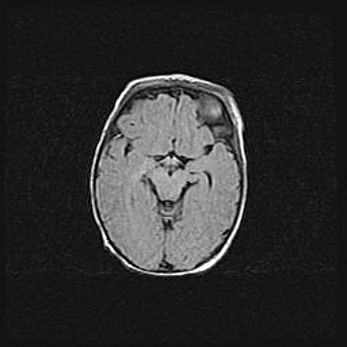

Церебральная ишемия II.

Возраст: 5 дней

Вес: 3400 г

Пол: женский

Окружность головы: 35 см

Срок гестации: 39 недель

Церебральная ишемия – это заболевание, характеризующееся недостаточностью (гипоксией) либо полным прекращением (аноксией) снабжения мозга кислородом по причине закупорки одного или нескольких сосудов. Это приводит к  что метаболическим расстройствам различной степени тяжести в тканях головного мозга, развитию коагуляционных некрозов и гибели нейронов.